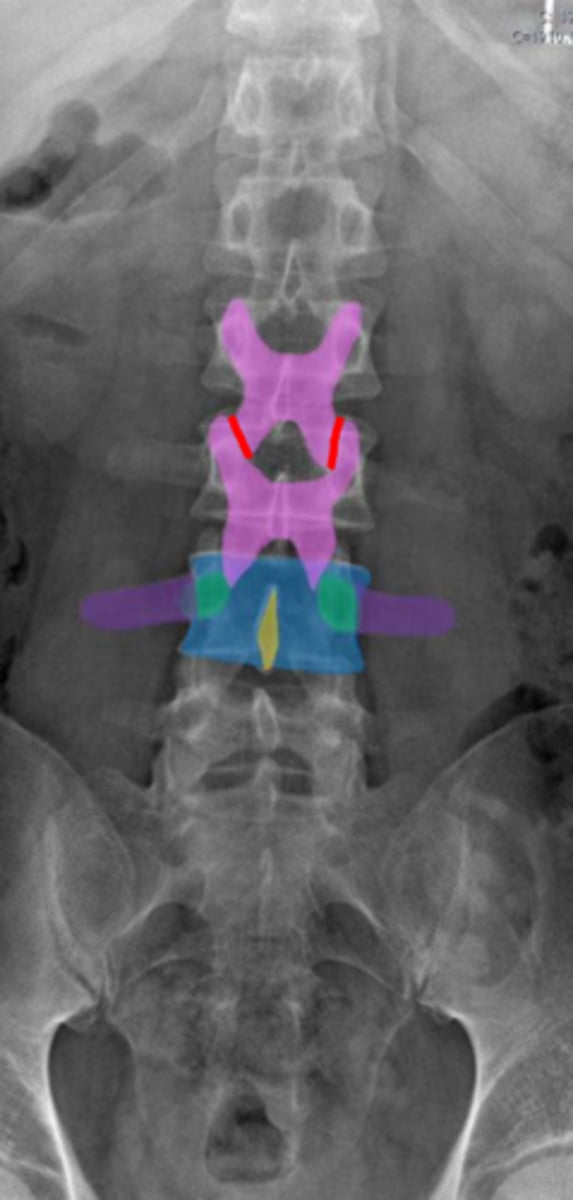

lumbar

What vertebrae is being examined?

lumbar vertebral body

Identify the blue structure

pedicles

Identify the green structure

transverse processes

Identify the purple structure

spinous processes

Identify the yellow structure

joint space between superior and inferior articulating facets

Identify the red line

intervertebral foramen

Identify the orange structure